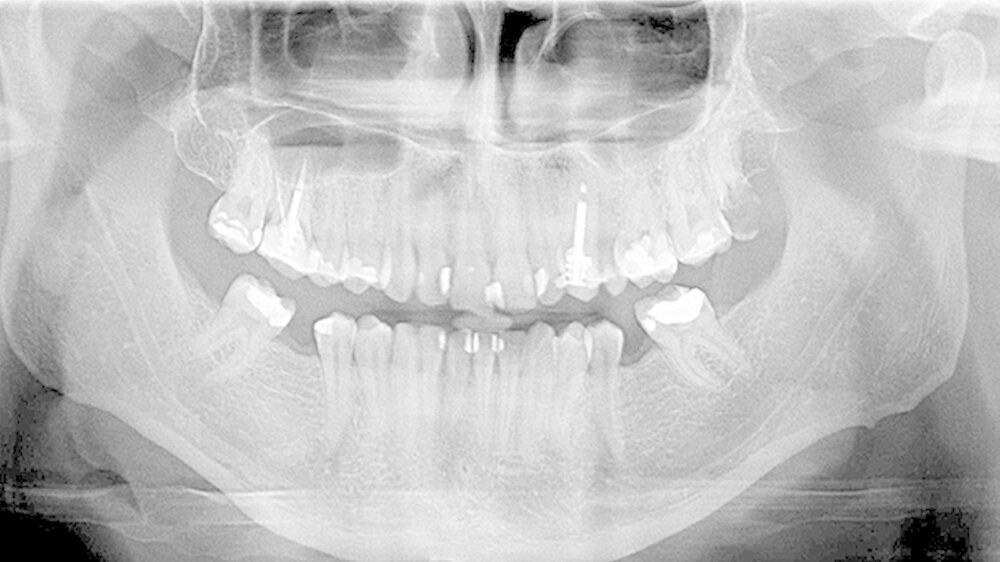

Der 28-jährige Mann wurde von seiner Hauszahnärztin zur Extraktion eines koronal zerstörten 8ers in die oralchirurgische Praxis überwiesen. Ein Röntgenbild wurde nicht mitgeliefert. Erhardt fertigte daher ein OPG an, doch zeigt das (Abbildung 2) nicht, was gleich kommen würde: Am Ende hing ein Doppelwhopper an der Zange!